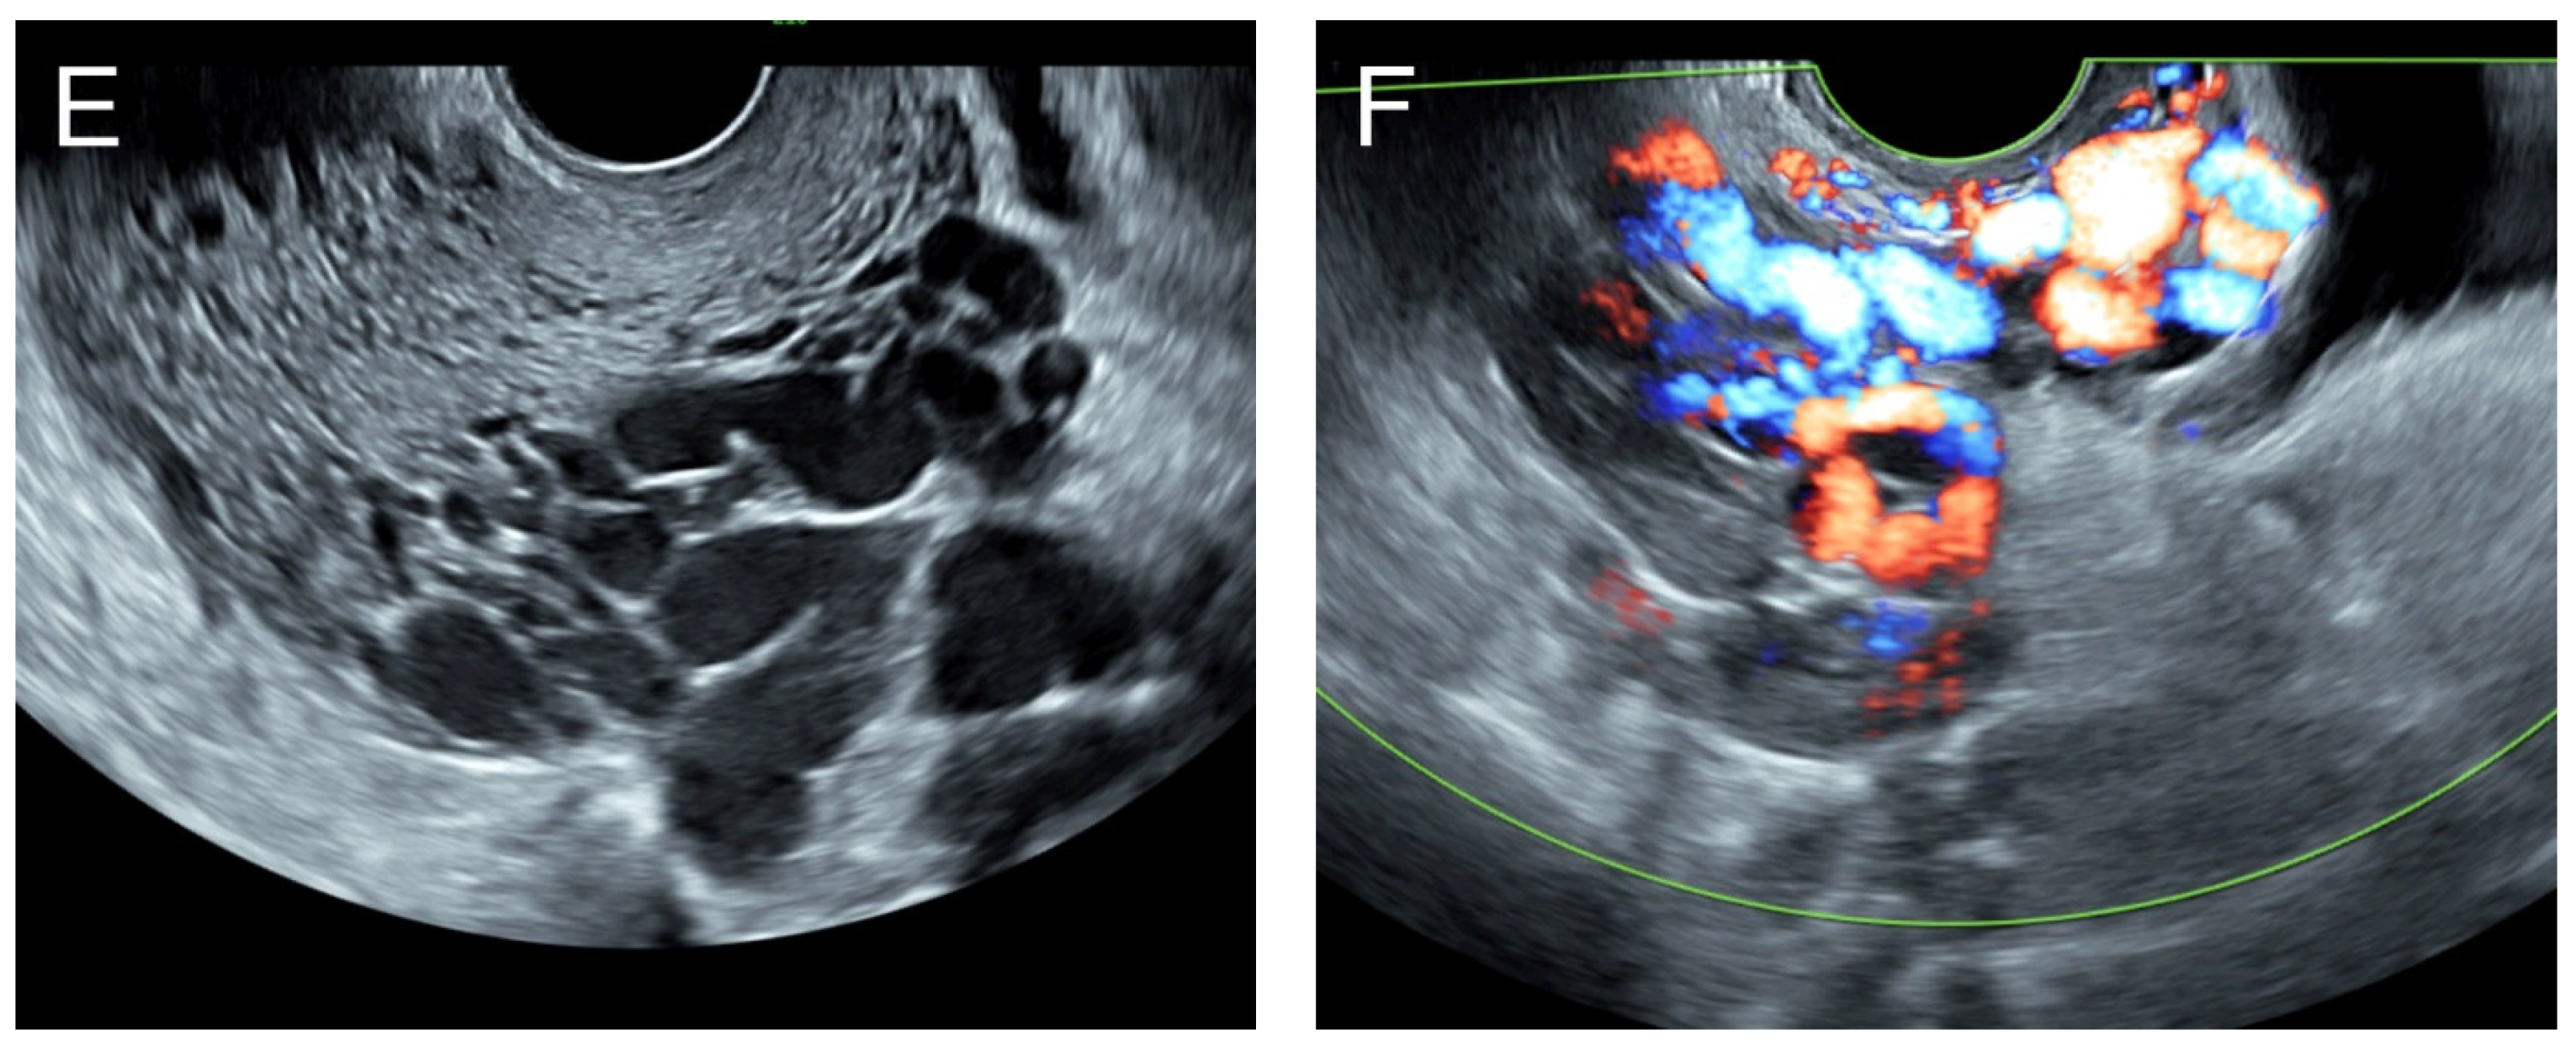

(A,B) Grayscale ultrasound and color flow mapping transabdominal sagittal scans of the left lower quadrant showed a markedly enlarged and tortuous course of the left uterine artery, with a high peak systolic velocity of 60 cm/s in spectral Doppler waveforms. (C,D) Sagittal scans of the uterus in transvaginal grayscale ultrasound and color flow mapping showed numerous anechoic/hypoechoic tiny tubular structures within the myometrium, which tended to head to the endometrium in the direction perpendicular to the endometrial line. These tubular structures were scattered all over the uterus and strongly vascularized throughout the uterus. (E,F) Sagittal scans of the left adnexa in transvaginal grayscale ultrasound and color flow mapping showed a markedly enlarged and tortuous course of the left uterine artery.